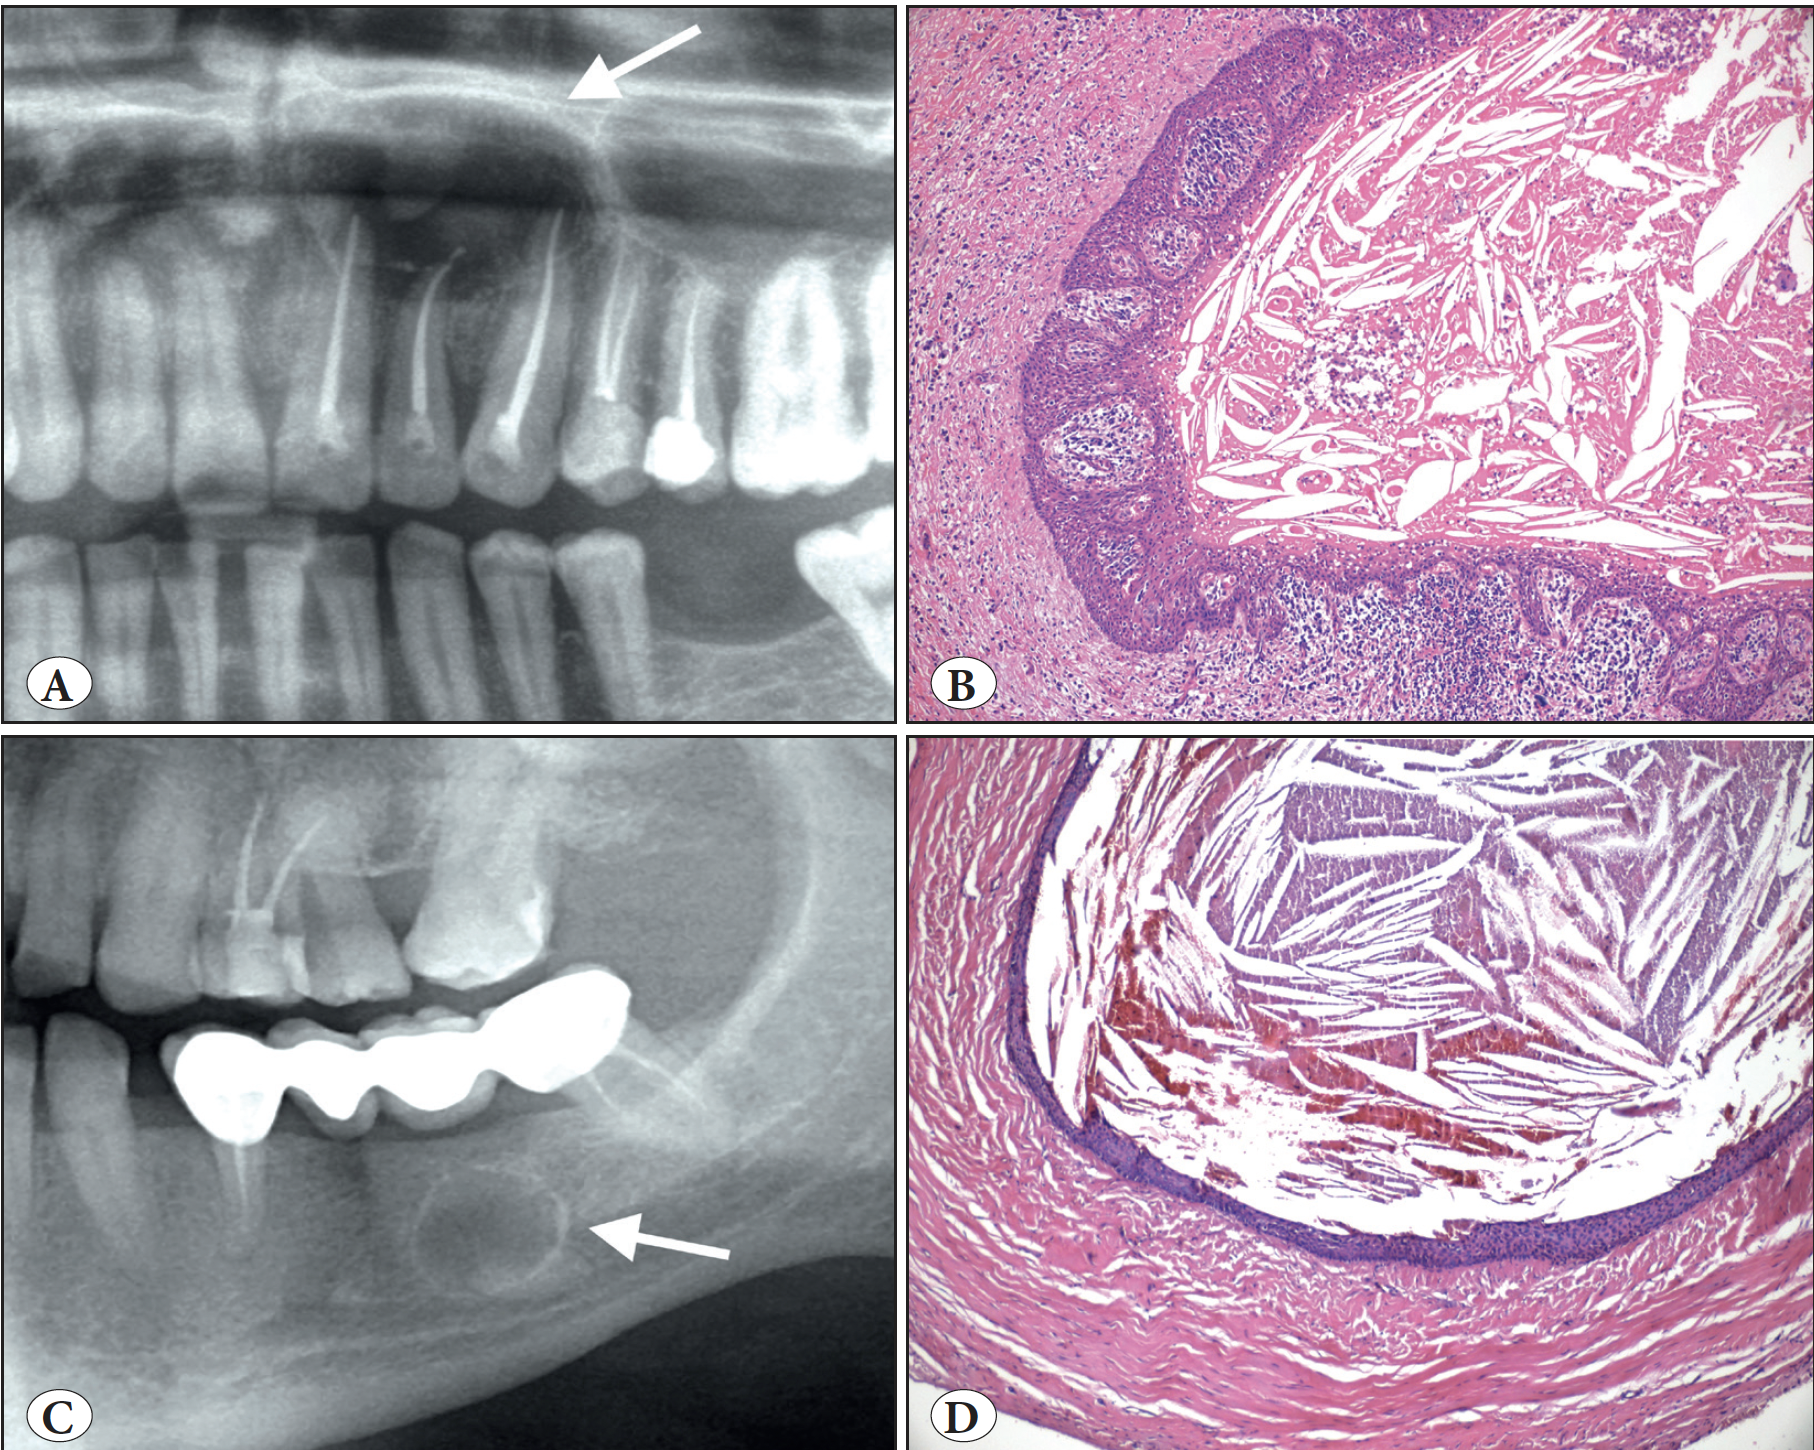

Nang do răng calci hoá (calcifying odontogenic cyst, COC)

COC tiếp tục có mặt trong phân loại nang với những thay đổi quan trọng liên quan đến định nghĩa có ảnh hưởng đến tiêu chuẩn chẩn đoán (diagnostic criteria). So với định nghĩa năm 2017, "biểu mô giống u nguyên bào men" (ameloblastoma-like epithelium) được loại bỏ, COC hiện nay được định nghĩa là nang do răng phát triển đặc trưng mô học là các tế bào ma thường calci hoá (a developmental odontogenic cyst characterized histologically by ghost cells, which often calcify). Trong khi hầu hết COC vẫn có biểu mô giống u nguyên bào men, đặc điểm này đã được loại bỏ khỏi các đặc điểm chính yếu trong chẩn đoán COC. Đột biến CTNNB1 mã hoá cho beta-catenin cũng được thêm vào bệnh sinh (pathogenesis) của COC.